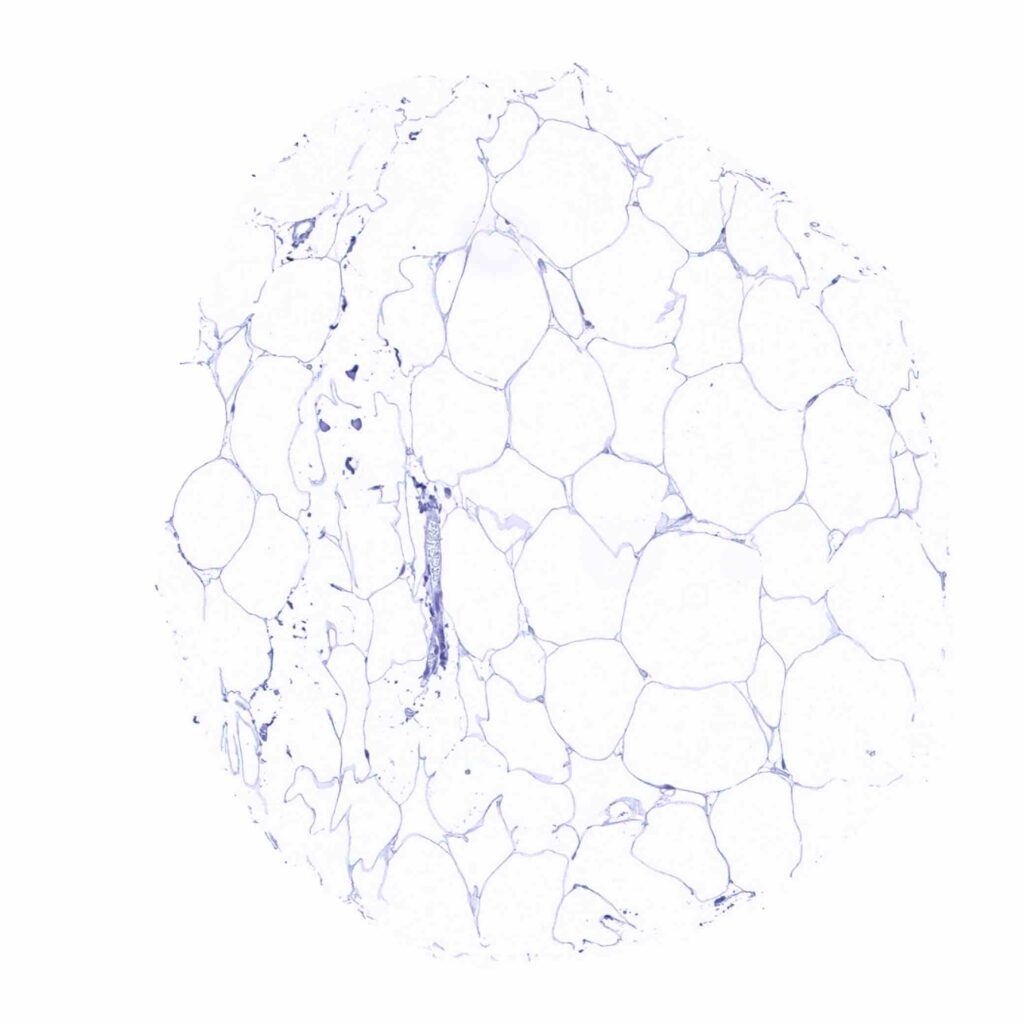

Fat